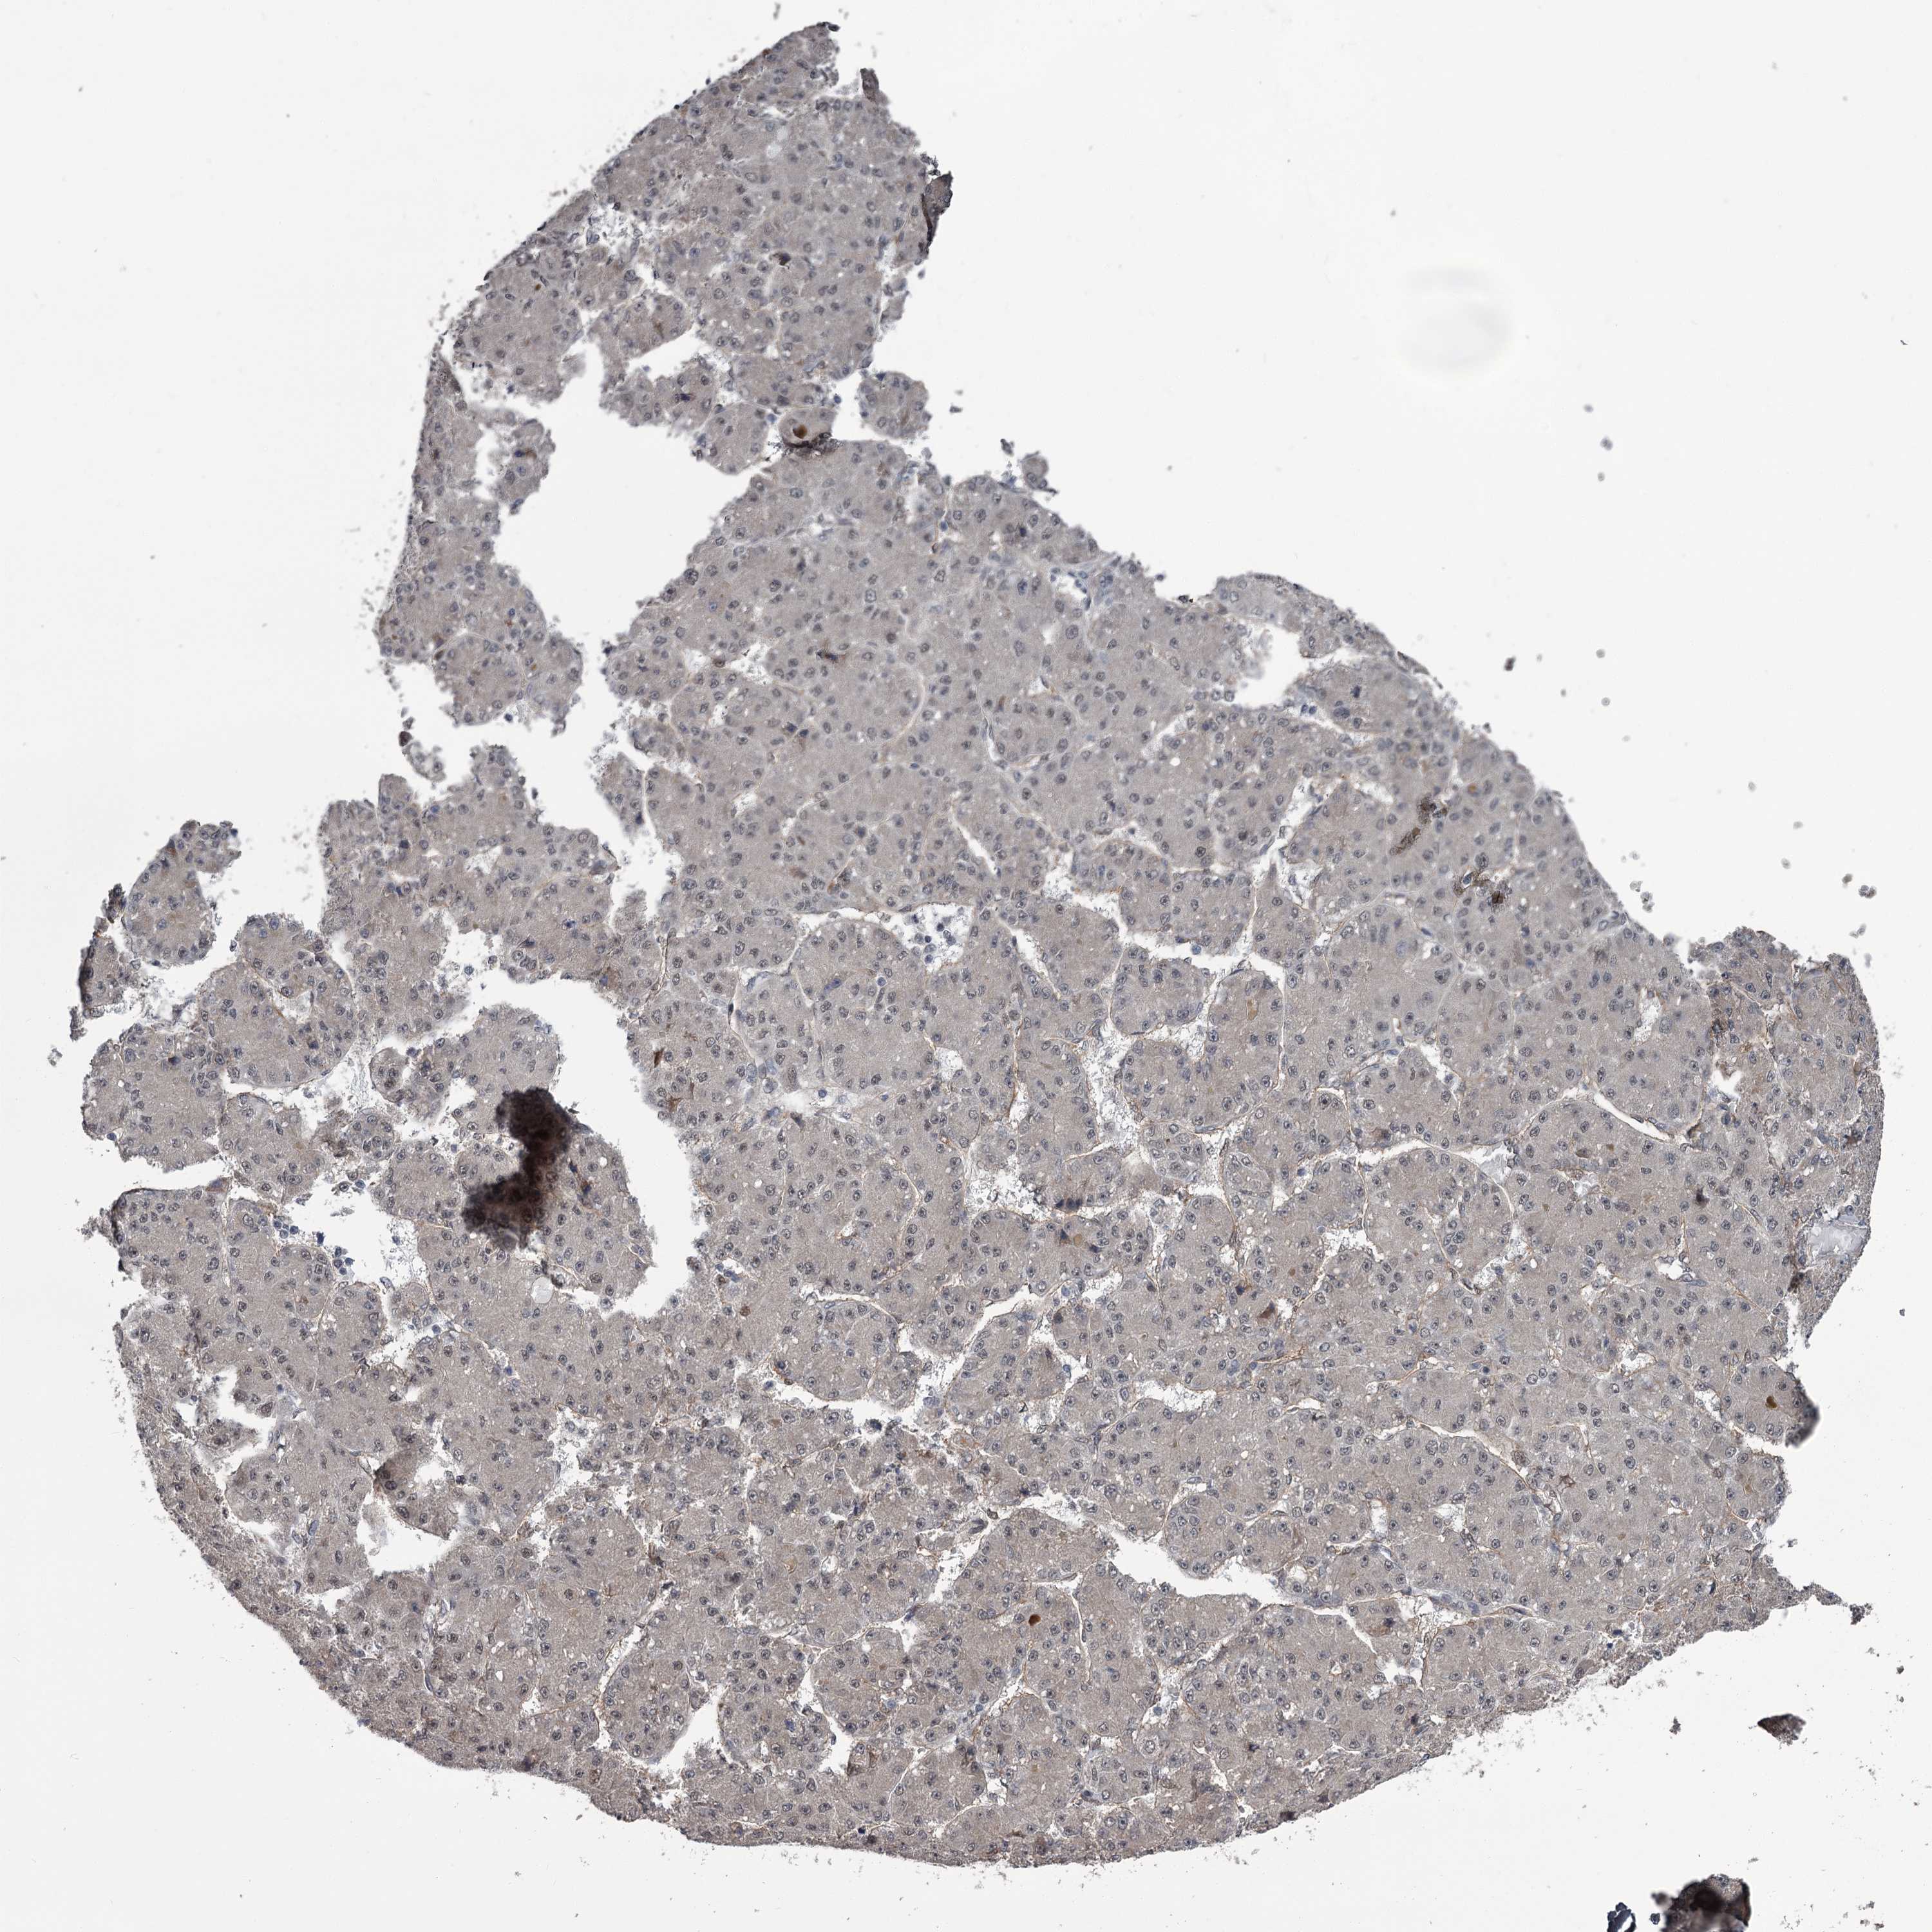

LIVER CANCER - Protein expressioni

A mouse-over function shows sample information and annotation data. Click on an image to view it in a full screen mode. Samples can be filtered based on level of antibody staining by selecting one or several of the following categories: high, medium, low and not detected. The assay and annotation is described here.

Antibody stainingi

Antibody staining in the annotated cell types in the current human tissue is reported as not detected, low, medium, or high, based on conventional immunohistochemistry profiling in selected tissues. This score is based on the combination of the staining intensity and fraction of stained cells.

Each image is clickable and will lead to virtual microscopy that enables deeper exploration of all samples and also displays staining intensity scores, fraction scores and subcellular localization as well as patient and tissue information for each sample.

Antibody HPA038562

Staining

High

Medium

Low

Not detected

Intensity

Strong

Moderate

Weak

Negative

Quantity

>75%

75%-25%

<25%

None

Location

Nuclear

Cytoplasmic/membranous

Cytoplasmic/membranous,nuclear

Cholangiocarcinoma

Carcinoma, Hepatocellular, NOS